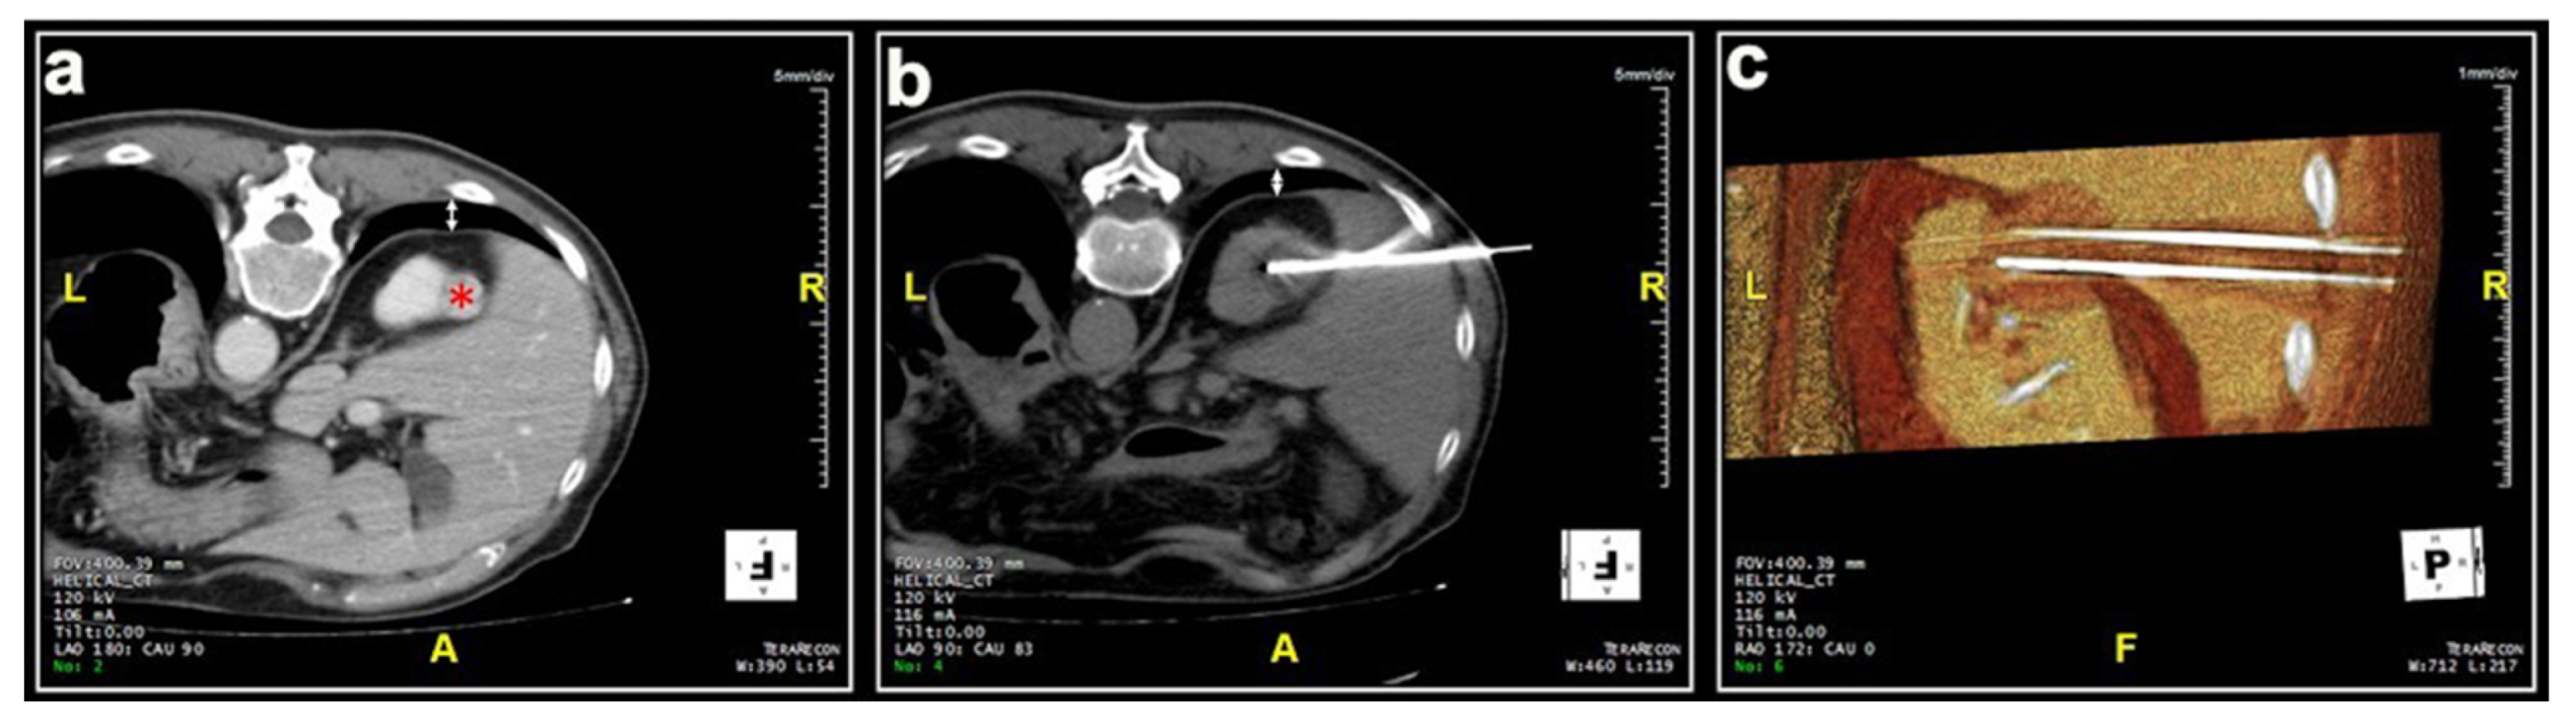

Most patients (87.4%) were treated prone. Twenty patients were treated in the oblique or lateral decubitus position (Figure 1). Only two treatments were carried out with the patient supine. Local anesthesia was mostly sufficient for the large majority of the procedures and mild conscious sedation was administered if needed. One patient required general anesthesia for the impossibility to collaborate with breath holds during the procedure because of dementia. In most cases, one lesion was treated in each procedure. In five patients, two lesions were treated in the same procedure, and, in another two patients, three lesions and four lesions were treated in a unique procedure, respectively. A median of two cryoprobes were used for each intervention (range: 1–8). Eight cryoprobes were required for the treatment of one of the largest tumors (5.4 cm), which revealed to be a clear-cell carcinoma at biopsy. The procedure was technically successful, and no complications occurred. Eighty-nine lesions required a complex cryoprobe approach. Hydro-dissection was necessary for the treatment of 13 tumors due to the vicinity of the bowel that could not be displaced after changing the position of the patient (Figure 2). In two cases, emptying of a cyst adjacent to the lesion was deemed necessary. Only one patient required a trans-hepatic approach (Figure 3). The procedures had a median duration time of 84 min (range: 40–153). Data on radiation exposure was available for 113 out of 138 patients with a median radiation exposure of 43.7 mSv.

Figure 1. Male, 73 years old. (a) Preparation of the treatment of a lesion located at the upper pole of the left kidney (*). The initial scan shows the interposition of the costophrenic sinus (white arrow). (b) The patient was positioned in an oblique decubitus, on the same side of the costophrenic sinus, to free the path for the two cryoprobes and the lesion was adequately treated without pneumothorax.